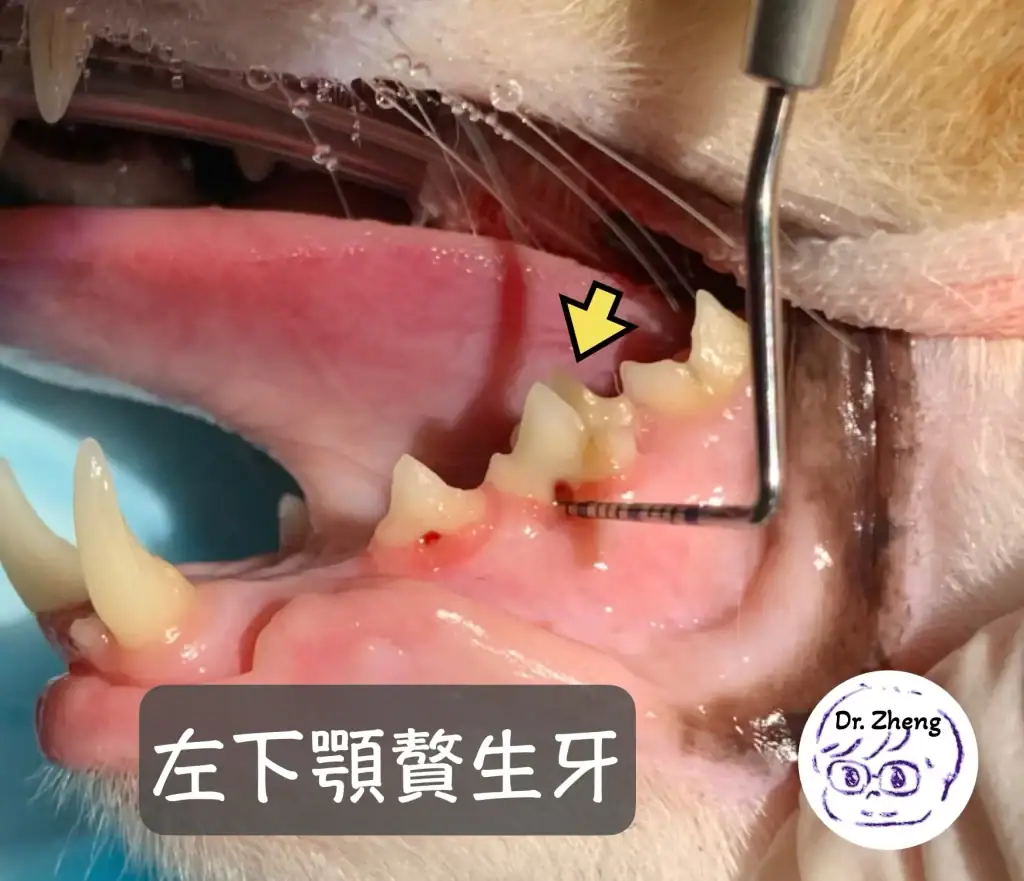

門診檢查紀錄:發現貓咪贅生牙!(Supernumerary teeth)

但再更仔細察看,竟然兩邊下顎都多一顆牙!(見下圖)

*正常下顎後排牙齒只會有3顆,而虎斑卻有4顆牙!這多餘的牙齒也可以稱作多生牙!這是發育上的異常!